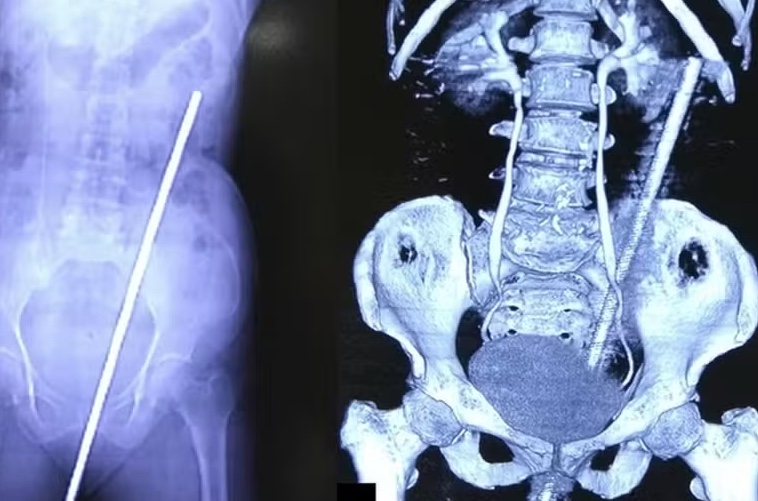

Uma mulher indiana de 65 anos passou por um susto e um procedimento médico inusitados após ser empalada por uma barra de ferro enferrujada de quase 60 centímetros. O acidente, que ocorreu em um campo próximo à sua casa, foi relatado no International Journal of Surgery Case Reports.

A vítima estava levando sua vaca para pastar em um dia chuvoso e escuro quando escorregou e caiu sobre a barra, que estava parcialmente enterrada no solo. A força do impacto fez com que o objeto perfurasse o reto da mulher e se estendesse até as costas.

Apesar da gravidade do ferimento, a equipe médica responsável pelo caso relatou que não houve danos a órgãos internos ou vasos sanguíneos. A mulher foi submetida a uma cirurgia de duas horas para a remoção da barra e recebeu tratamento com antibióticos e vacina contra o tétano para prevenir infecções.